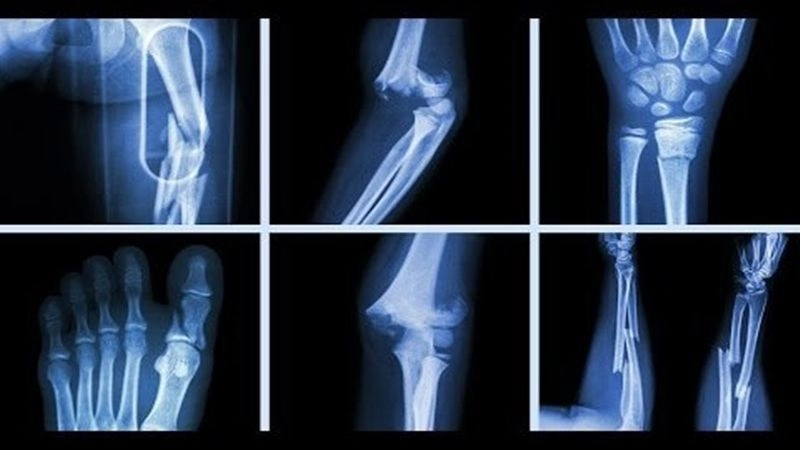

Gãy xương là tình trạng xương bị biến dạng, gãy đôi theo chiều dọc hoặc chiều ngang hoặc gãy thành nhiều phần. Một người có thể gặp chấn thương này ở bất kỳ khu vực nào trên cơ thể nếu chịu tác động lực quá mức. Ngoài ra, để thúc đẩy quá trình hồi phục diễn ra nhanh chóng, người bệnh nên được thăm khám bác sĩ ngay khi bị chấn thương hoặc phát hiện các dấu hiệu xương bị gãy.

Gãy xương là tình trạng xương bị biến dạng

Các vị trí dễ bị gãy xương

Gãy xương sườn: thường xảy ra do chấn thương ở ngực khi bị ngã, tai nạn xe cộ hoặc lúc chơi thể thao, tai nạn xe, lúc chơi thể thao, quá trình sinh mổ bác sĩ có thể phải xoay thai để đảm bảo an toàn cho trẻ sơ sinh, vô tình tạo áp lực lên xương sườn và gây gãy…

Gãy xương đòn: nguyên nhân phổ biến nhất gây ra tình trạng này là ngã chống tay. Lúc này, vai va chạm mạnh trực tiếp gây gãy hoặc gián tiếp gãy trong tư thế duỗi khuỷu, dạng vai

Gãy xương cẳng tay: xuất hiện khi chịu lực trực tiếp như bị đánh, tai nạn giao thông (nguyên nhân trực tiếp), duỗi thẳng tay ra để chống khi (nguyên nhân gián tiếp)…

Gãy xương cẳng chân: xảy ra do tai nạn lao động, tai nạn giao thông, chấn thương thể thao, các bệnh lý về xương…